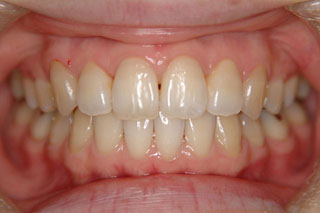

2年半ほどの治療で、装置を撤去し保定治療に移行しています。概ね緊密な臼歯の咬合と前歯の被蓋が確立されました。

保定治療を開始してから2年半が経過していますが、良好な咬合の安定が維持されています。見た目だけではなく、中心位マウントの咬合器にて顎位のズレを計測していますが、計測値は1mm未満の数値である事を確認しています。理想的には中心位=咬合位かも知れませんが、多少の遊びは必ず出てきます。しかしながら最初からルーズなゴールを目指していたら、的を外してしまうでしょう。できれば、ピンポイントで理想を目指したいものです。